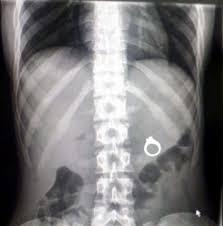

Los niños mayores y los adolescentes tampoco escapan al manejo de monedas u objetos pequeños. A fin de demostrar habilidades suelen ser llevados a la boca y por un simple empujón o broma de sus amigos fácilmente son deglutidos. En algunas oportunidades estos sucesos no son informados a los padres hasta que la duda o el temor llevan a ser divulgados. Es en ese instante donde la familia decide consultar a la guardia. La radiografía no se hace esperar, comprobándose generalmente la situación del objeto en el abdomen, en plena recorrida del tubo digestivo. El mismo finalmente es eliminado por la materia fecal provocando regocijo en el niño y sus padres.

Se conocen casos en los cuales la moneda había quedado detenida en la garganta colocada en bisel. Adherida a las paredes de la misma provoca tos irritativa. Mediante una radiografía de cuello la imagen redondeada típica aparece en la zona del cuello sorprendiendo a todos.